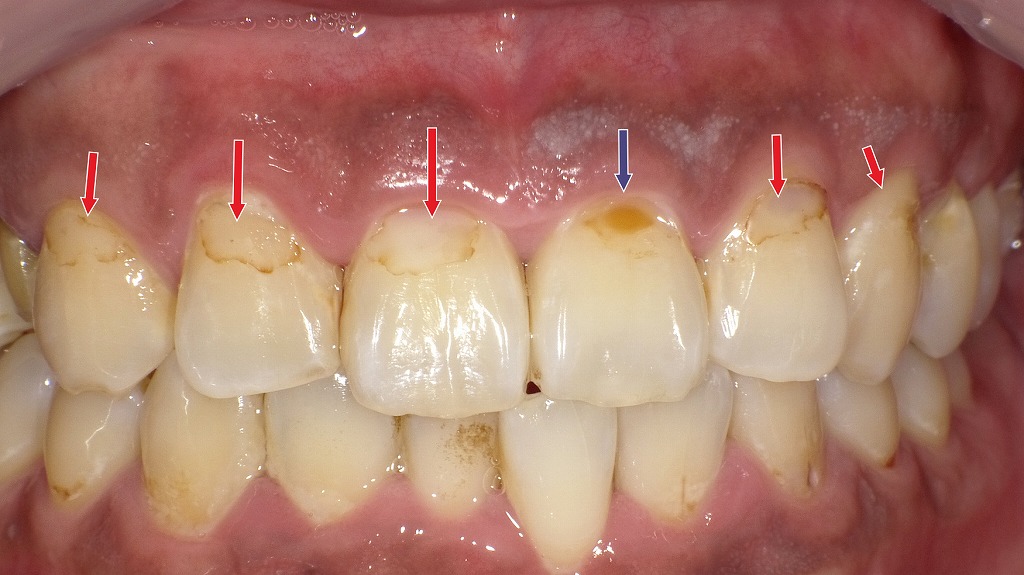

経年劣化したコンポジットレジン修復:変色・褐線・脱離の発生例

赤矢印は、コンポジットレジン修復の“辺縁部”に生じた褐線(マージンステイン)を示しています。経年劣化によりレジンの微小な隙間に色素が入り込み、変色として現れています。

青矢印は、一部のレジンが脱離した部位を示しており、再治療が必要な状態です。レジン修復は時間の経過とともに摩耗や着色が起こるため、定期的なチェックが重要です。